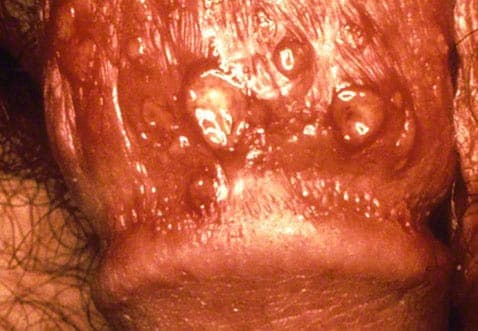

Symptomerne på herpes genitalis kan vise sig som røde væskende blærer, der dannes på kønsdelene, lår og/eller ved endetarmen. Herpes sår/blærer kan være smertefulde eller give svie og kløe. Når de væskefyldte blærer brister, bliver de til sår, der heler i løbet af to-tre uger uden ardannelse. Hvis du er usikker på, om du lider af herpes genitalis, er det bedst, at du taler med din læge og får stillet en diagnose.

Herpes på penis er typisk i udbrud på forhuden. Penis vil oftest være rødlig og øm. Som for kvinder vil der opstå blærer der omdannes til sår når de brister.

Som de fleste vira udvikler herpes sig i stadier. Det første stadie er karakteriseret ved at huden bliver rød og skaller af. I andet stadie kommer små blærer til syne, der bliver efterfulgt af væskende sår i tredje stadie og tørre skorper i det fjerde stadie. Det sidste stadie er helingsprocessen, hvor sårskorperne gradvist forsvinder./p>